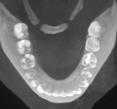

Figura 1. Fotografías intraorales y lateral de cráneo. A. Vista lateral (VL) derecha en oclusión. B. Vista frontal (VF) en oclusión. C. VL izquierda en oclusión. D. Radiografía lateral de cráneo.

Figura 2. Fotografías oclusales y ortopantomografía. A. Vista de la arcada superior. B. Vista de la arcada inferior. C. Ortopantomografía.

Reporte de caso clínico

Paciente masculino de 10 años, se presenta a la consulta en la clínica Gnathos, la mamá reporta desagrado en la estética dental y facial del paciente. En la exploración clínica se observa mordida profunda, amplio número de piezas dentales con caries, fracturas dentales, mala higiene y encías inflamadas. presenta clase II división 2, se le indicaron estudios complementarios para diagnóstico asertivo, modelos de estudio,

Tratamiento de mordida profunda

radiografía panorámica y lateral de cráneo, fotografía intraoral y extraoral, historia clínica y consentimiento informado.